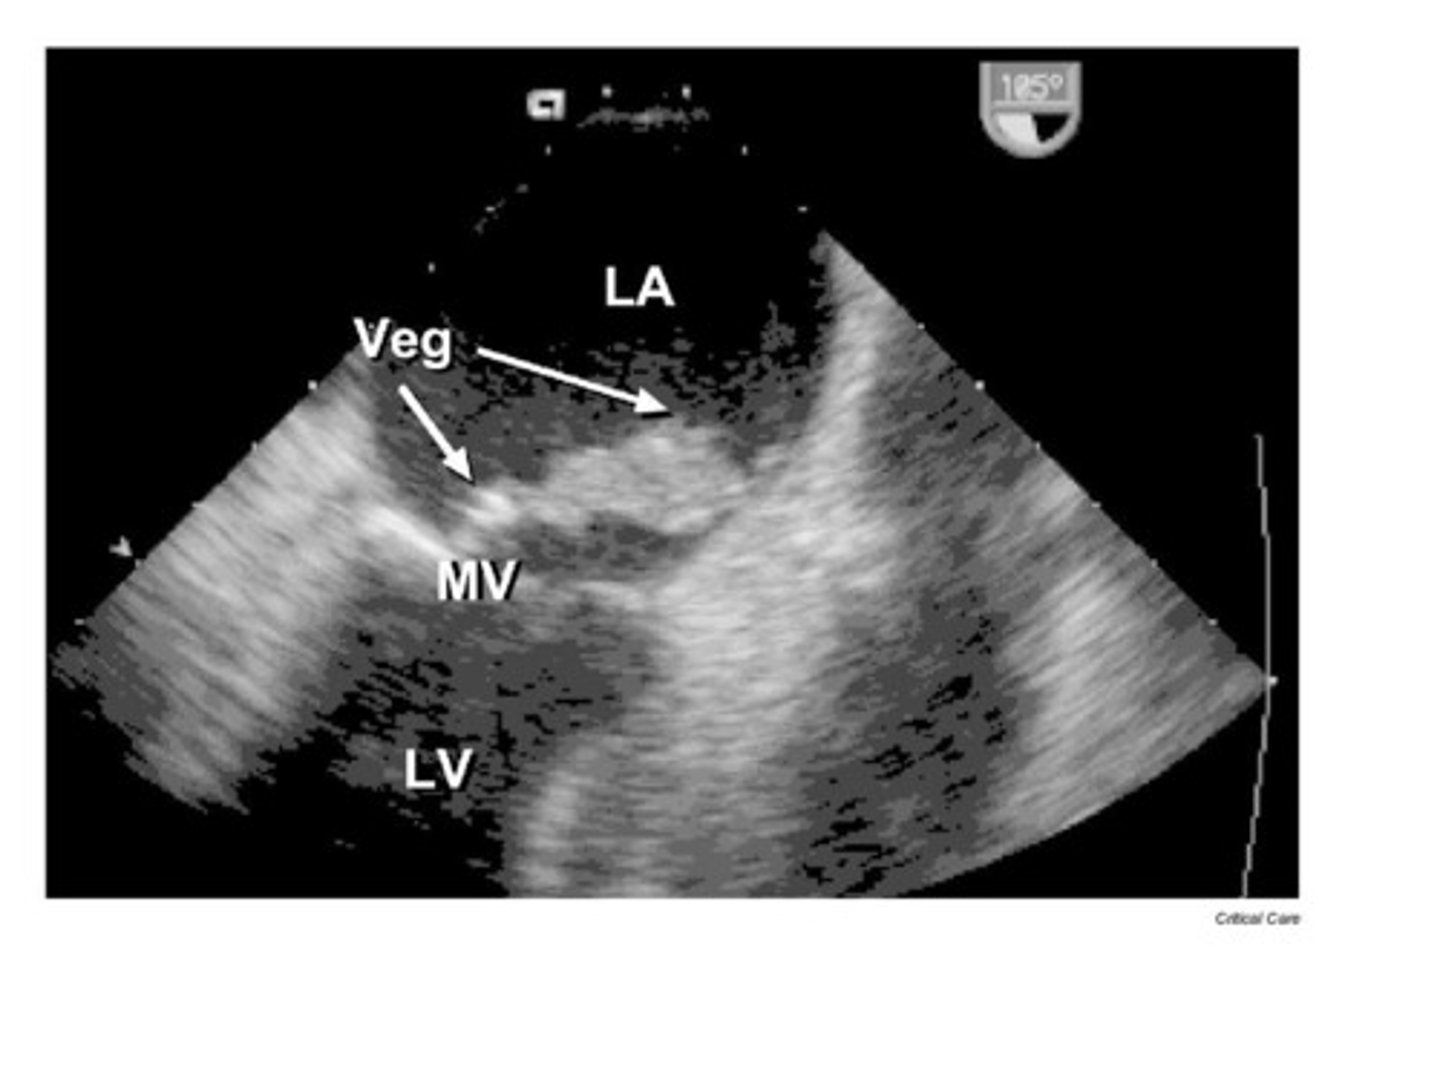

An infection of the inner lining of the heart and heart valves that may cause vegetations or perforations of the valves is known as:

myocarditis

epicarditis

endocarditis

pericarditis

Looking at the color map on the image, the red color represents:

flow toward the transducer

flow away from the transducer

This image is demonstrating which type of color flow?

normal color flow

disturbed flow

spontaneous flow

steady flow

The blue color is demonstrating which of the following?

the transducer has nothing to do with the direction of flow